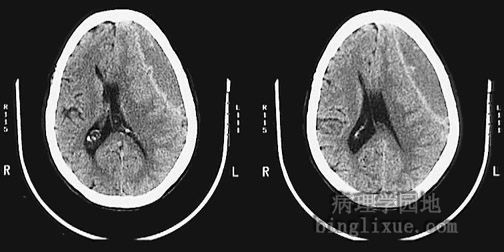

非增强CT显示左侧硬膜下血肿,脑组织推向右侧,脑室变窄。

These are two views of the same sagittal head CT scan without contrast demonstrating a large subdural hematoma with left to right shift and ventricular narrowing.

非增强CT显示双侧硬膜下血肿,可见右侧血肿更大。

This is a sagittal head CT scan without contrast demonstrating bilateral subdural hematomas, the right greater in size than the left.